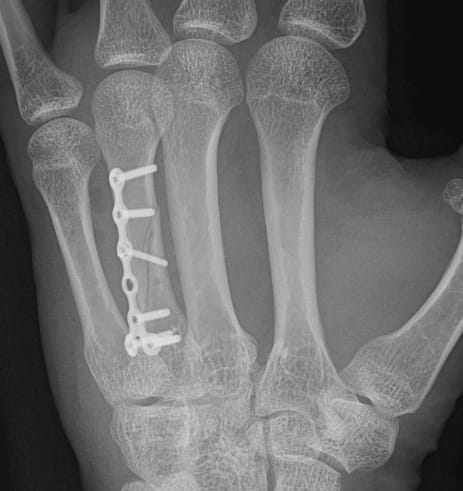

Organo muy expuesto a sufrir lesiones como las fracturas de falanges y metacarpianos, artrosis de los dedos o dedos en resorte.

Proyectos Médicos

Avances en cirugía de mano y muñeca para mejorar vidas.